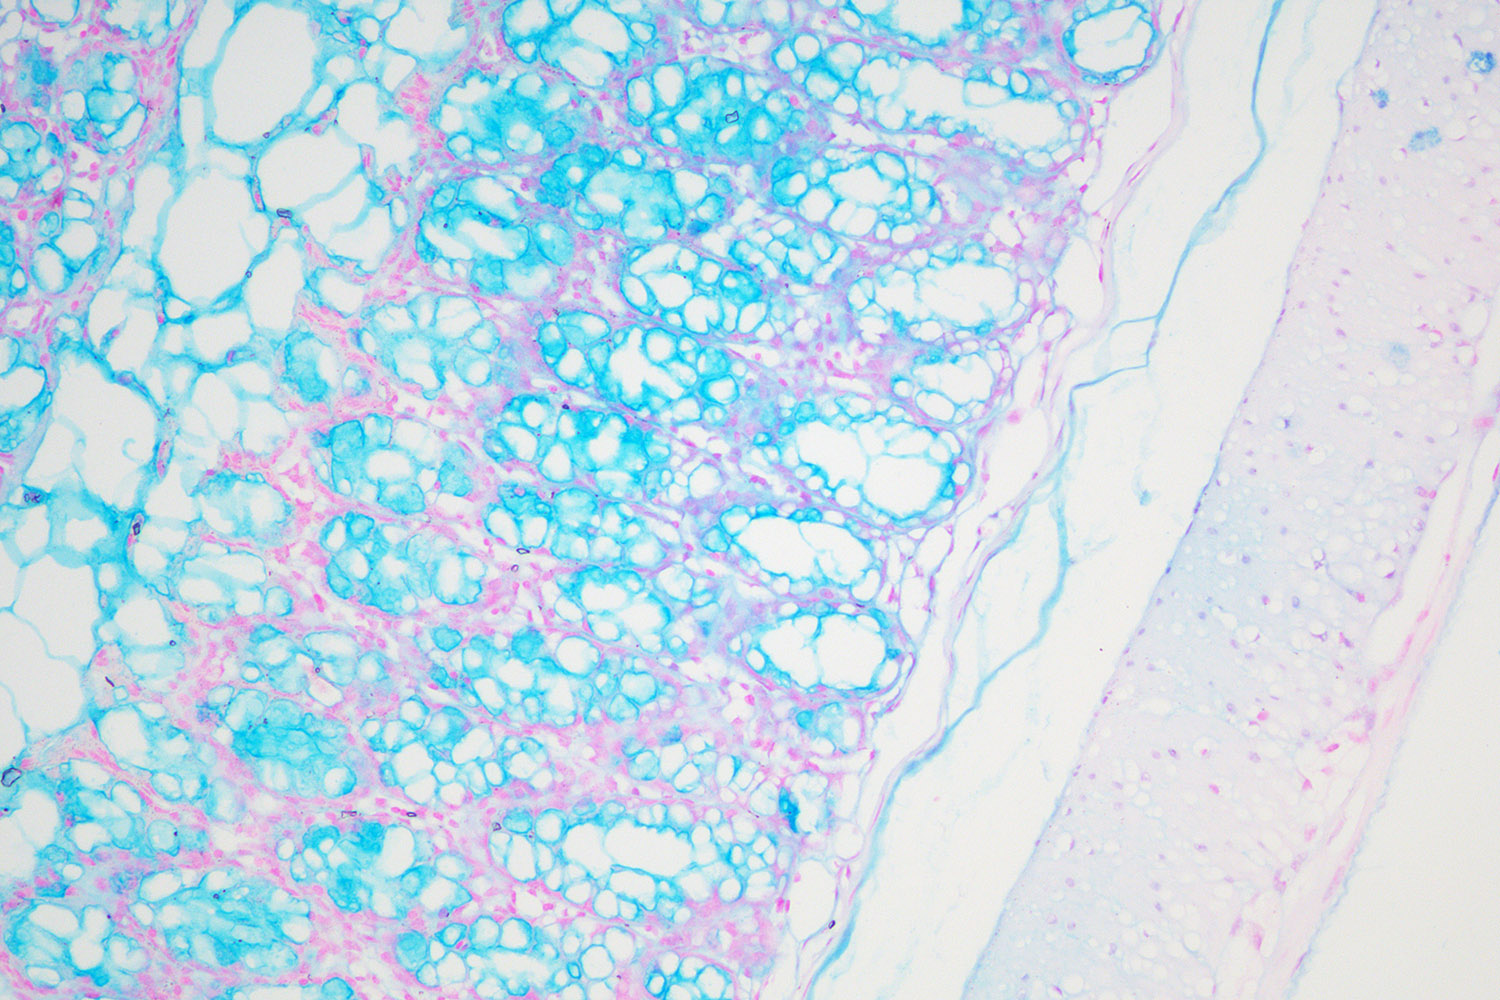

阿利新蓝(又称阿尔辛蓝﹑爱先蓝等)和PAS技术联合使用可鉴别同一组织中的中性黏蛋白和酸性粘蛋白。这种技术也常用作广泛检测黏蛋白的手段,切片先经标准阿利新蓝染色再使用PAS技术。阿利新蓝可将唾液黏蛋白﹑硫黏蛋白和蛋白多糖染成蓝色。PAS技术可将中性黏蛋白染成深红或紫红色,同时将既含中性黏蛋白又含酸性黏蛋白的组织和细胞染成深浅不同的紫色,这是由于阿利新蓝与Schiff试剂结合并发生反应。上述染色常可出现在含有中性黏蛋白和唾液黏蛋白的笑场杯状细胞中。阿利新蓝的染色原理在于是类铜钛花青染料,这种阳离子染料与酸性基团结合,也即阿利新蓝与组织内含有的阴离子基团如羧基和硫酸根形成不溶性复合物。分子中带正电荷的盐键与酸性粘多糖物质中带负电荷的酸性集团结合形成不溶性的复合物而呈蓝色,再与PAS进行复合染色,就能显示三种不同黏液物质成分。